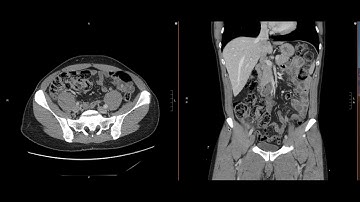

Abdominal Imaging Call Prep Cases: Acute Uncomplicated Appendicitis (CT) Case 3 Discussion